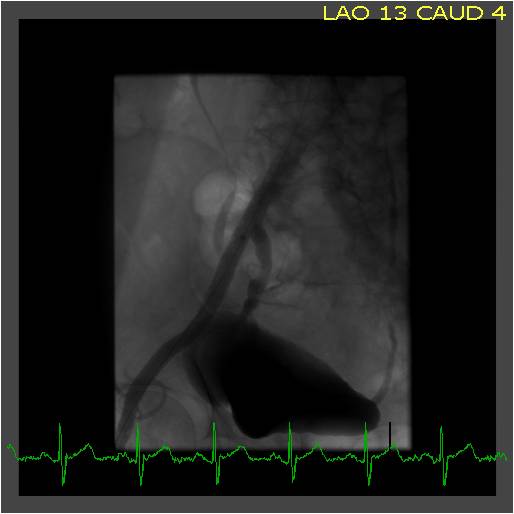

You perform an angiogram on a 64 year-old man with lifestyle-limiting claudication. An eccentric, calcified 60{8ceaa46882e4d49283ff23b35262537230ad541262f55a031ead545e66522058} stenosis originating in the right common iliac and extending to the right external iliac artery is identified.

There is an associated 40 mm Hg pressure gradient across this lesion. You successfully cross the lesion in retrograde fashion from right femoral artery access. You then perform balloon angioplasty with good results yielding a 20{8ceaa46882e4d49283ff23b35262537230ad541262f55a031ead545e66522058} residual stenosis, no evidence of dissection, and no evidence of distal embolization. Should stenting be performed, and if so, what type of stent should be selected?